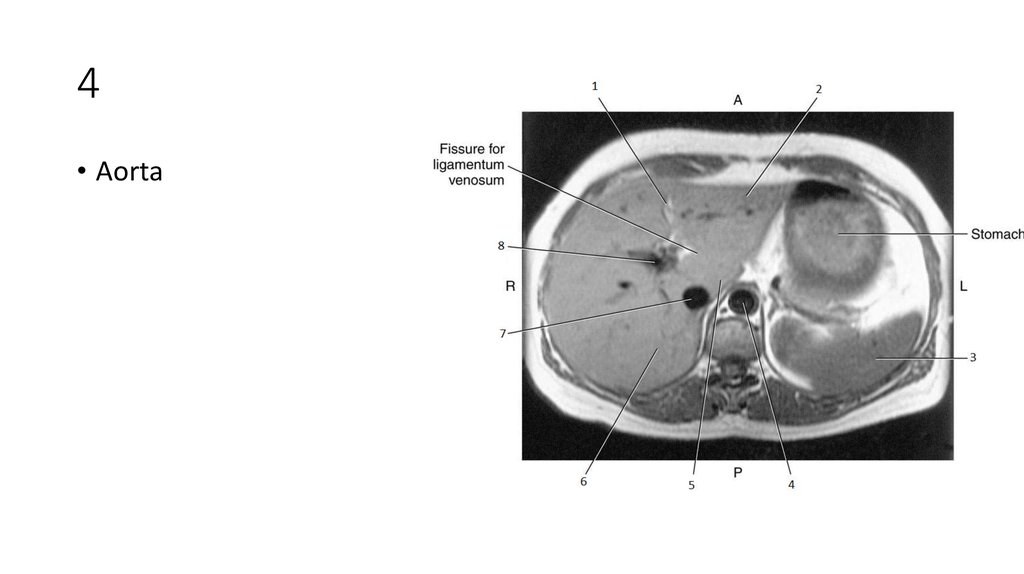

22. 4

23. 4

• Aorta

24. 5

25. 5

• Caudate Lobe of Liver

26. 6

27. 6

• Right Lobe of Liver

28. 7

29. 7

• Inferior Vena Cava (IVC)

30. 8

31. 8

• Portal Vein

32. 1

33. 1

• Intrahepatic Ducts

34. 2

35. 2

• Pancreatic Duct

36. 3

37. 3

• Common Bile Duct